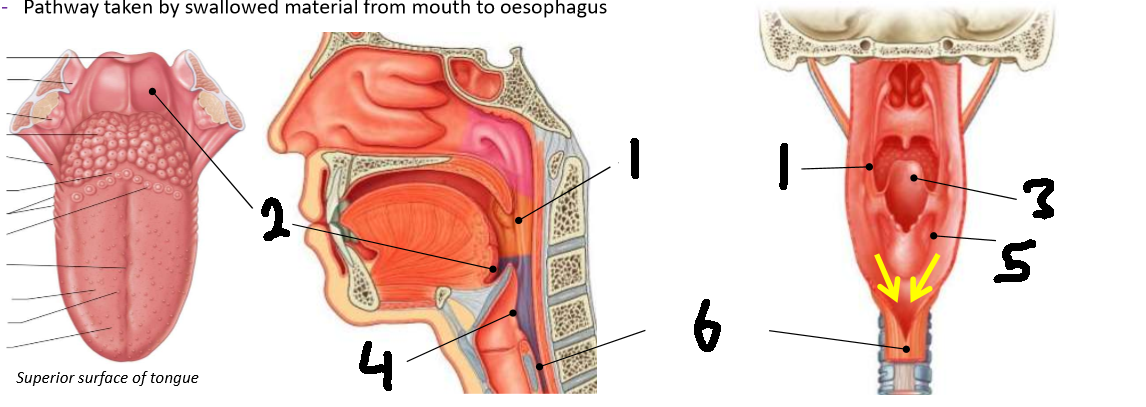

What is 1?

palatopharyngeal arch

What is 2?

vallecula

What is 3?

epiglottis

What is 4?

laryngeal inlet

What is 5?

piriform fossa

What is 6?

oesophagus